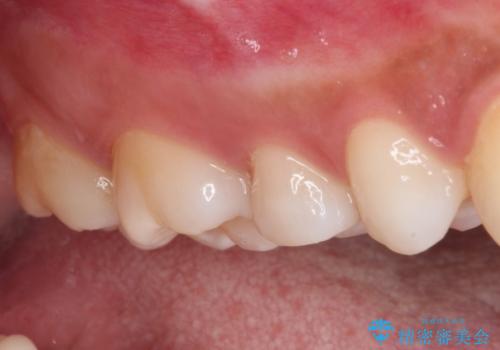

まずは虫歯を除去した上で根管治療を行い、部分矯正により骨内深い位置にまで及んだ健全な部分を引っ張り出すこととしました。

その後骨形成処置を行い、治癒を待って補綴治療を行うこととしました。

かなり深い位置にまで虫歯が及んでいたため、かなりの量を引っ張り出す必要があり、残された歯根は短く小さい状態となりました。